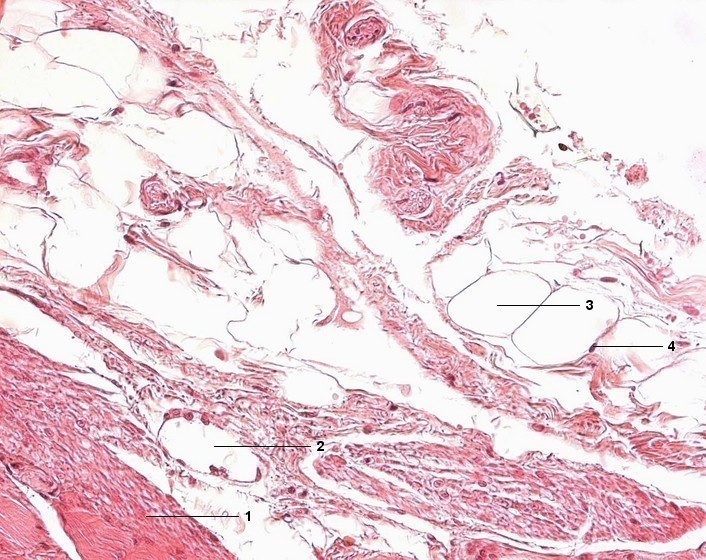

1 Tunica muscularis, Stratum longitudinale

2 Tunica adventitia, Venole

3 Univakuoläre Fettzelle, Fettvakuole

4 Zellkern der Fettzelle